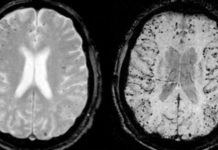

Major Study: Cancer and Sunscreen Myth Exposed

As indicated by a June 2014 article included in The Independent (UK), a noteworthy report directed by analysts at the Karolinska Institute in Sweden...